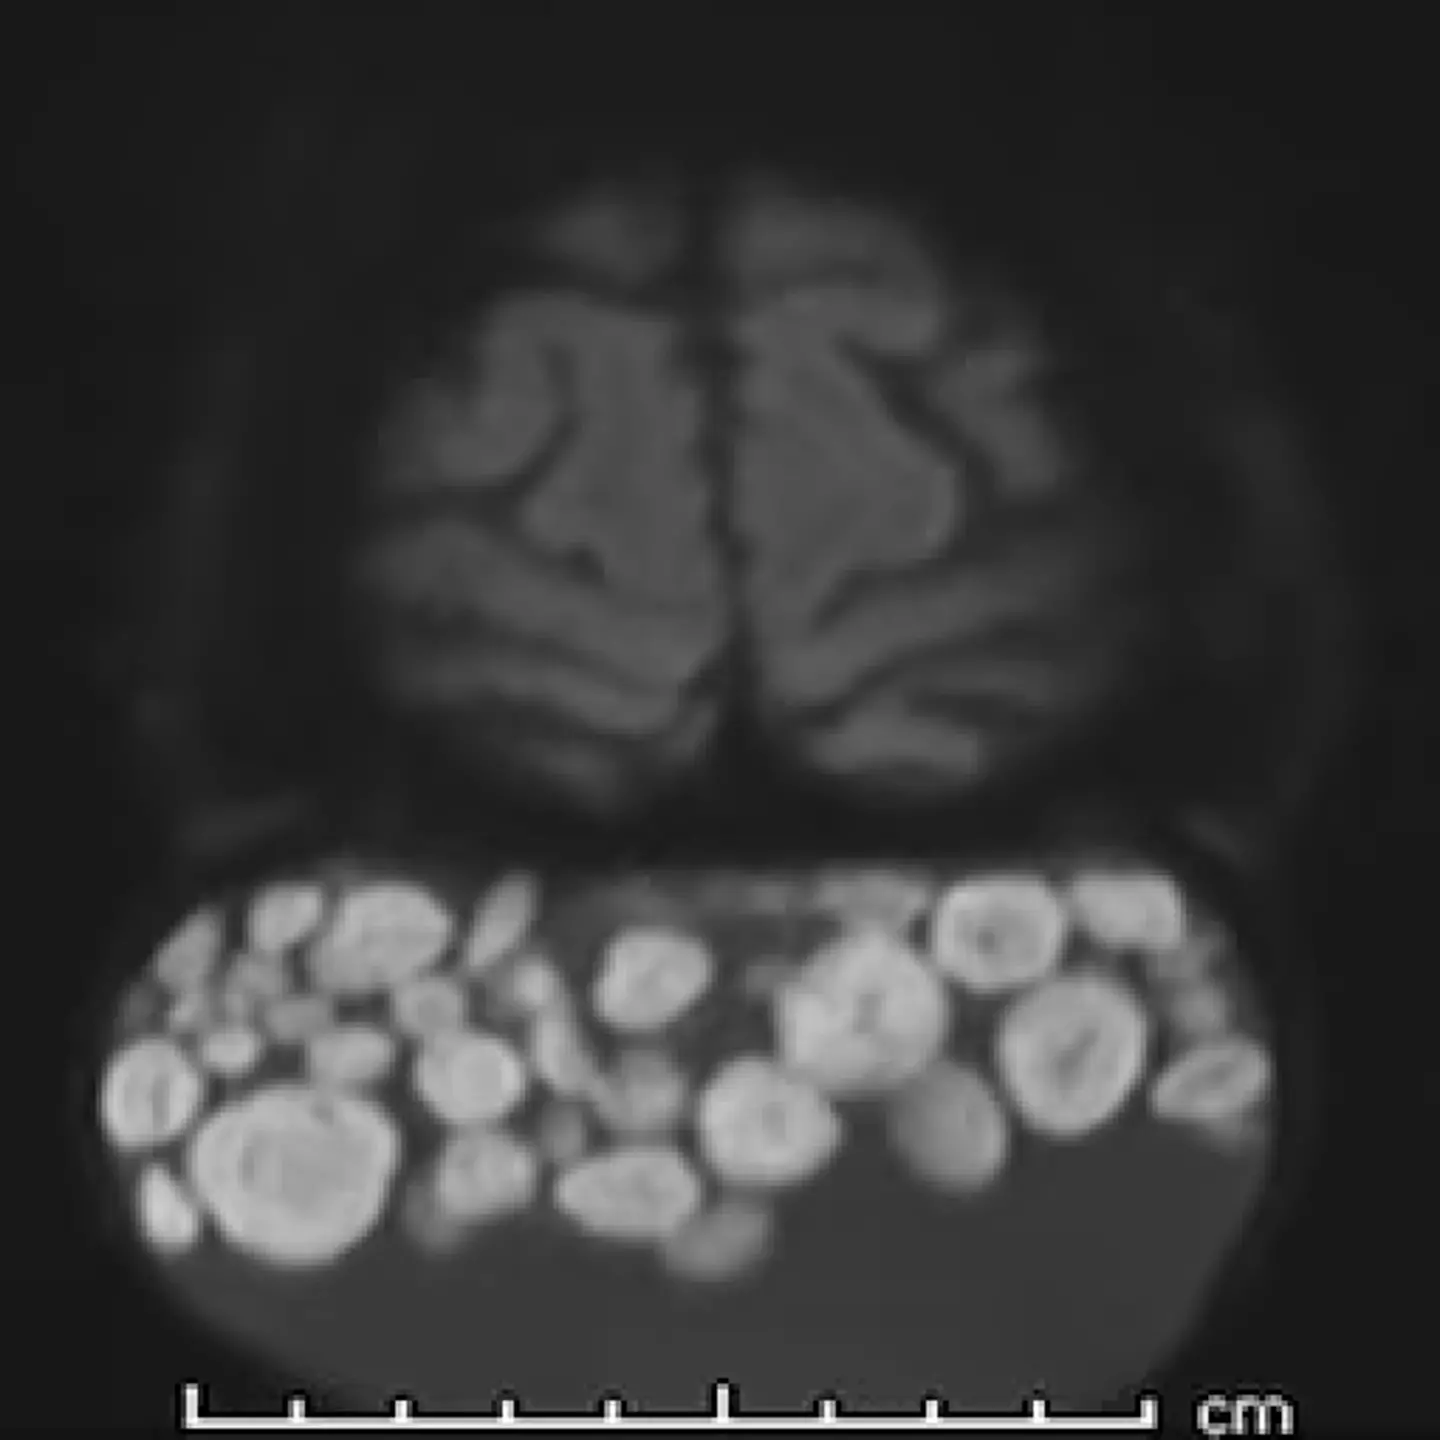

Upon further inspection they discovered dozens of balls of keratin, which looked like marbles, inside the growth - which was hidden at the back of her scalp behind her hair.

"The 'marbles' are spherical aggregates of keratin, fat, sebaceous material, fibrin, and hair floating within the fluid matrix of the cyst.

"Though uncommon, the 'sack of marbles' sign is considered pathognomonic of mature cystic teratomas in the head and neck."